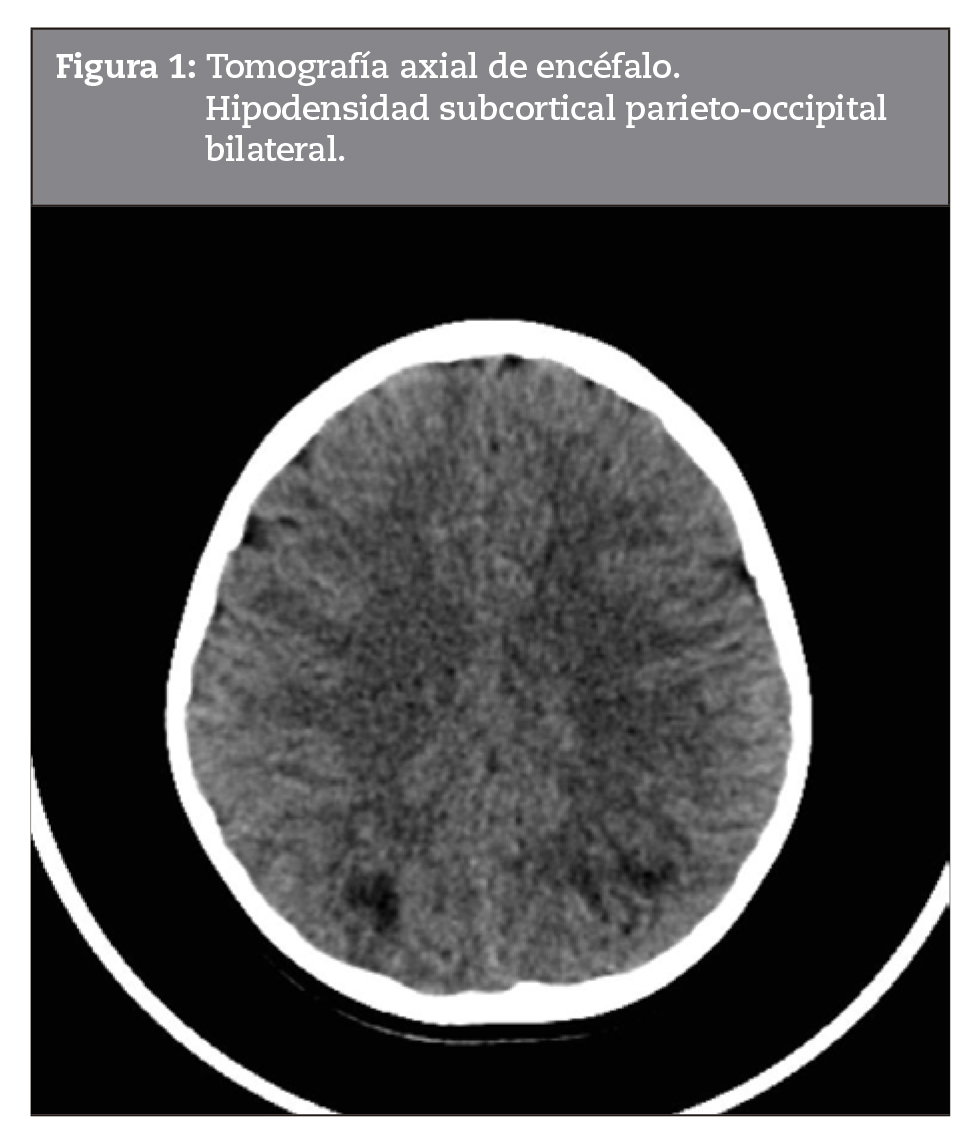

Al inicio de la pandemia por SARS-CoV2 en Argentina, un niño de 5 años de edad consulta a un hospital general de la provincia de Buenos Aires por dolor abdominal intenso, vómitos, diarrea y petequias en miembros inferiores de 5 días de evolución, con hematuria microscópica y cilindros hemáticos, sin fiebre. Se descarta conducta quirúrgica (ecografía abdominal que informa engrosamiento parietal a nivel de fosa ilíaca derecha) y se sospecha VIgA/PSH, por lo cual recibe dexametasona 0,6 mg/k/día endovenosa con mejoría del cuadro abdominal y resolución de la hematuria. A las 48 horas de su internación presenta melena con descenso del hematocrito sin descompensación hemodinámica y convulsión tónica clónica generalizada asociada a registros de hipertensión arterial interpretada como emergencia hipertensiva; se le realiza tomografía computada de cerebro (TC) (Figura 1) con hallazgos presuntivos de síndrome de encefalopatía posterior reversible (posterior reversible encephalopathy syndrome, PRES), por lo cual se lo deriva al Hospital de Alta Complejidad en Red El Cruce.

Debido al antecedente de convulsión, se realiza fondo de ojo normal, resonancia magnética nuclear (RNM) de cerebro (Figura 3), donde se observa hiperintensidad de señal en sustancia blanca subcortical parietal bilateral en flair y T2, sin realce luego de la administración de gadolinio y sin cambios en coeficiente de difusión aparente (apparent diffusion coefficient, ADC), pudiendo corresponder a lesiones secundarias a vasculitis.

Los estudios por imágenes se emplean para descartar otras patologías y para conocer el alcance de la enfermedad. Frente a la expresión clínica de nuestro paciente, los estudios realizados demostraron compromiso vascular de los órganos afectados. Los patrones de neuroimagen más frecuentemente encontrados en niños con afectación neurológica asociada a infección por SARS-CoV-2 fueron similares a la encefalomielitis diseminada aguda, como en nuestro caso. Las complicaciones neurovasculares son menos frecuentes que en adultos y la mayoría evoluciona favorablemente14. Las nuevas técnicas de RM (como inversión-recuperación con atenuación del líquido cefalorraquídeo, difusión, perfusión y angio-RM de alta resolución) aumentan la sensibilidad de la RM en esta patología15,16.